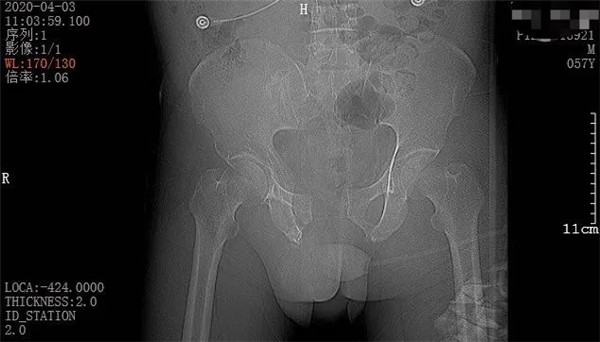

4月3日一早,和往常一樣,家住六橫的趙大叔騎著三輪車去買菜,誰(shuí)知經(jīng)過(guò)下坡路時(shí)剎車失靈,趙大叔重重地撞上了一根柱子后,三輪車壓倒了他身上。趙大叔頓時(shí)感覺(jué)身體疼痛不已,無(wú)法轉(zhuǎn)身、站立。在路過(guò)市民的幫助下,他迅速被送至當(dāng)?shù)蒯t(yī)院。經(jīng)CT拍攝顯示,趙大叔骨盆骨折、腹腔積血。此時(shí),大叔突然出現(xiàn)了呼吸急促、血壓不穩(wěn)定等情況,聞?dòng)嵍鴣?lái)的家屬當(dāng)即表示要到廣安醫(yī)院治療,并火速聯(lián)系車子送往我院。

二周后,趙大叔病情穩(wěn)定,身體各方面條件符合手術(shù)指征后,骨科中心副主任羅軍帶領(lǐng)手術(shù)團(tuán)隊(duì)為其進(jìn)行了骨盆骨折、恥骨聯(lián)合分離、雙側(cè)髂骨骨折、右側(cè)恥骨上下支骨折切開(kāi)復(fù)位內(nèi)外固定術(shù),手術(shù)一個(gè)半小時(shí)順利完成。